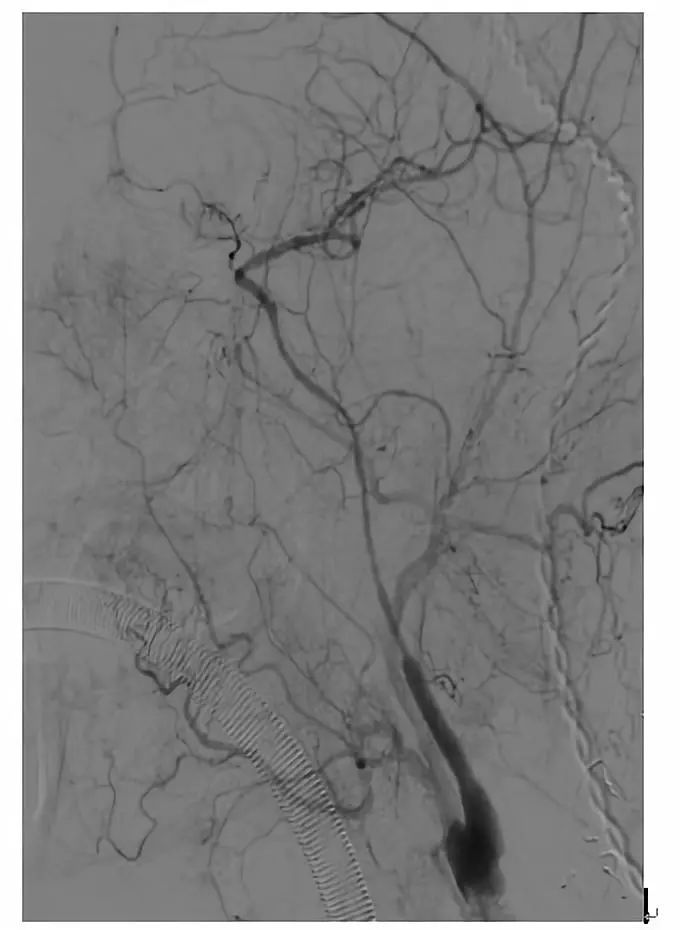

全麻下,血管造影显示右侧颈内动脉起始段完全闭塞,同侧眼动脉逆行充盈右侧颈内动脉,向近端反流到海绵窦上段同3月前的造影

先行颈动脉近端闭塞处切开并行内膜剥脱,再切口处置入动脉鞘后,用300cm 0.014微导丝交换出微导管用1.5mm×20mm gateway 行闭塞段扩张,造影显示右侧颈动脉闭塞段通畅

再使用3mm×20mm球囊行从上往下预扩张C2段三次,扩张后置入ENTERPRISE 支架4.5mm×28mm自膨支架两枚,经股动脉造影显示颈动脉全程完全畅通。复查CT未见新发梗死灶。